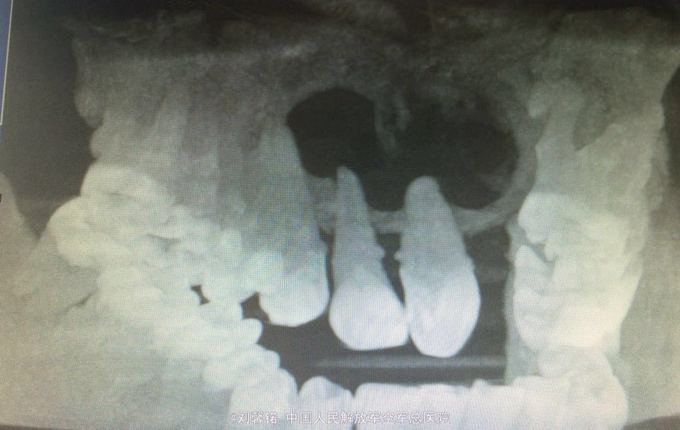

检查:右上唇鼻下区肿胀,口腔卫生差,牙石(+).21缺失,22-13前庭沟变浅,黏膜肿胀,牙不松动,无疼痛,舌.腭均侧有不同程度的膨隆,扪诊囊性感,牙髓活力,13~23分别为32.64.64.64.44辅助检查:cbct示:13~22根尖区卵圆形密度减低区,边界清楚,边缘光滑锐利,周围骨质吸收,囊腔壁为致密白线。囊肿上界与鼻底仅余薄层骨质.穿刺检查:穿刺液为草黄色液体